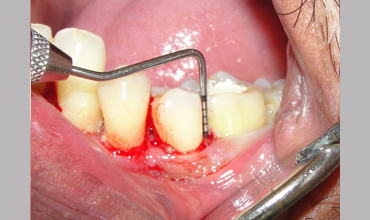

NON SURGICAL MANAGEMENT OF ENDODONTIC LESION AND SURGICAL MANAGEMENT OF PERIODONTIC LESION